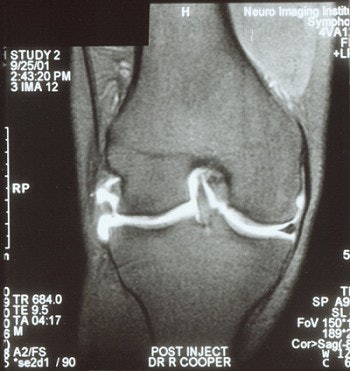

![]() |

| MR arthrogram is needed to demonstrate a meniscal tear in a patient with >25% meniscal resection. |